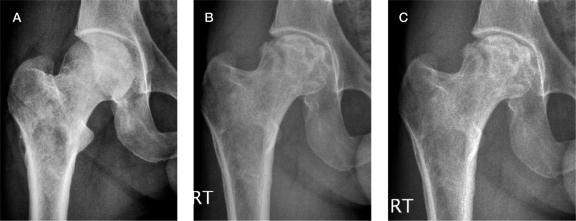

We retrospectively reviewed medical data from all patients who were recommended to undergo drilling for osteonecrosis of juxta-articular bone of the femoral head, the humeral head, or upper tibia for acute osteonecrosis at a pre-collapse stage.

11 patients (mean age 34 years) underwent drilling of 12 joints with juxta-articular osteonecrosis; 3 (mean age 51 years) refused intervention. 9 joints that were drilled showed advancing joint degeneration within 0.5 to 4 years. 3 joints have undergone replacement. Of the 3 joints that did not undergo drilling, 2 have undergone replacement and 1 has collapsed with osteoarthritis.

We found equally poor outcome with and without drilling. Effective intervention can only be achieved by improving our understanding of bone physiology and pathophysiology in Gaucher disease.

我们回顾性分析了所有因股骨头、肱骨头或胫骨近端关节周围骨急性坏死且处于塌陷前期而被建议进行钻孔治疗的患者的医疗数据。

11例患者(平均年龄34岁)接受了12个关节周围骨坏死的钻孔治疗;3例患者(平均年龄51岁)拒绝干预。接受钻孔治疗的9个关节在0.5至4年内出现了关节退变进展。3个关节已进行置换。在未接受钻孔治疗的3个关节中,2个已进行置换,1个已因骨关节炎而塌陷。

我们发现钻孔治疗与未钻孔治疗的结果同样不佳。只有通过增进对戈谢病骨生理学和病理生理学的理解,才能实现有效的干预。